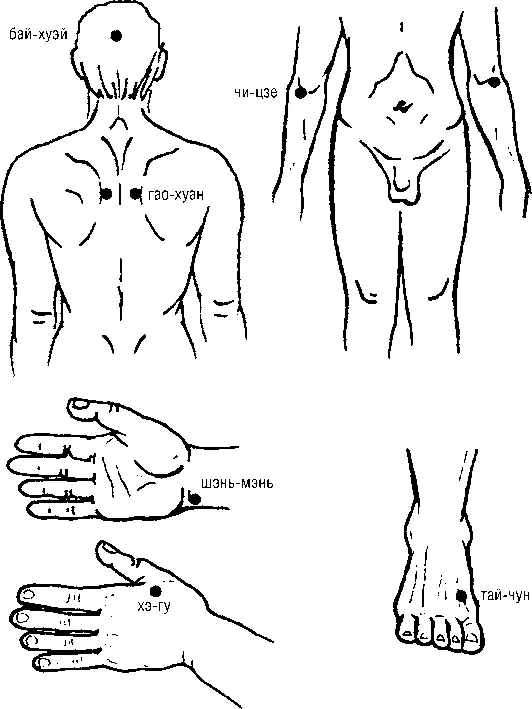

Рис. 114. При угнетенном, подавленном состоянии, глубокой печали, депрессии, неудовлетворенности в жизни, скорби

Точечный массаж выполняется по стимулирующей, тонизирующей, возбуждающей методике (рис. 114):

1. БАЙ-ХУЭЙ (Т-20) находится на вершине головы, на пересечении сагиттальной (от кончика носа вверх) линии, и фронтальной (от верхушки обеих ушных раковин).

2. ШЭНЬ-МЭНЬ (С-7) находится на локтевом крае предплечья в нижней трети, в углублении у проксимального края гороховидной кости и лучезапястной складки.

3. ХЭ-ГУ (GI-4) находится на тыльной стороне кисти: при сжатии первого и второго пальцев образуется возвышение, на вершине которого расположена искомая точка.

4. ЧИ-ЦЗЕ (Р-5) находится на поперечной складке локтевого сгиба, на месте литерального края сухожилия, двуглавой мышцы плеча.

5. ГАО-ХУАН (V-43) находится на 3 цуня наружу, между Д 4–5/2 отсрединной линии спины, по 2-й ее линии.